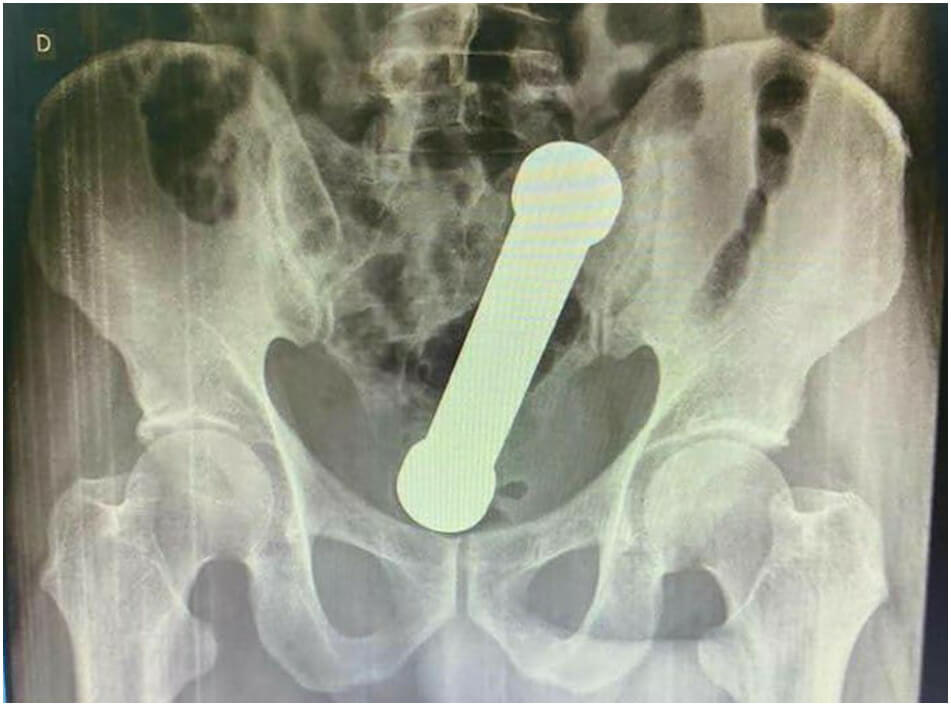

Göğüs ve karın radyografisinde, pnömoperitonyum yokluğu, inen, enine ve çıkan kolon anslarında hafif distansiyon ve rektosigmoid geçişte yaklaşık bir yerde egzersiz dambıl şeklinde yabancı bir cismin varlığının kanıtı

Bahse konu operasyona ilişkin ilgili makalede yer verilen görseller şu şekildeydi: